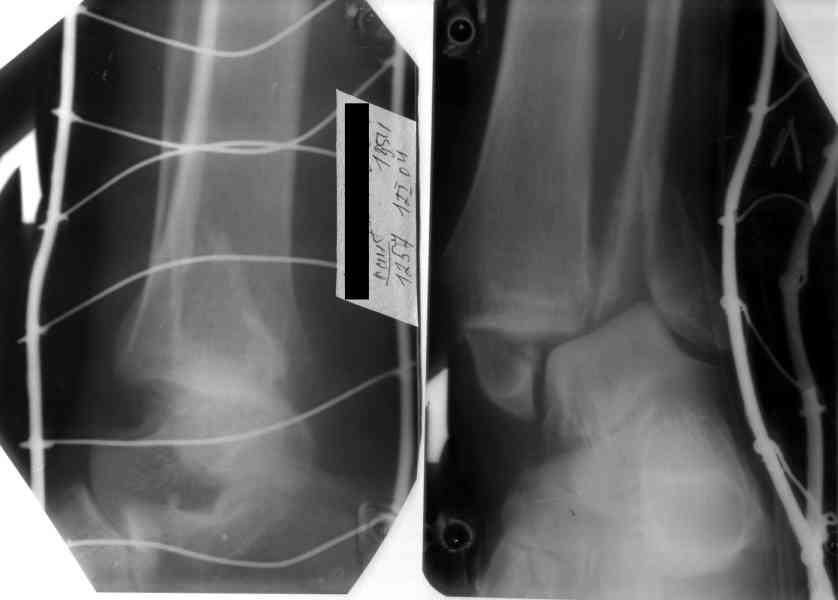

После проведенной дискуссии пришел к выводу, что трансартикулярная диафиксация не совсем приемлима с учетом современных методик остеосинтеза. Кроме того, вычитал, что хрящ разрушается на расстоянии до 0,5 см от места проведения спицы.

Пока я был в интернатуре, предпочитали осуществлять стабильный остеосинтез с ранней функцией. См. приложения и полнотекстный вариант

статьи.